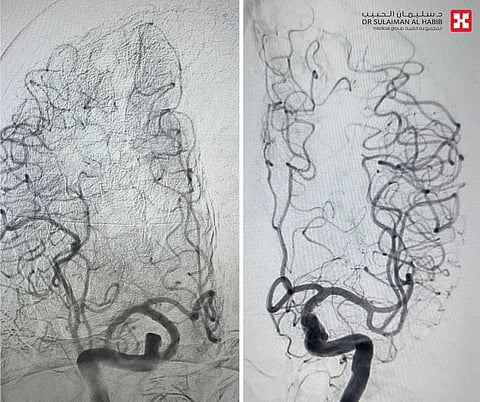

وقالت د. فرح؛ إن المراجع دخل عبر الطوارئ مشتكياً من أعراض عدة، أبرزها السقوط المتكرّر على الأرض، وعدم القدرة على المشي، بسبب الدوار والدوخة، وكذلك الغثيان والقيء والخمول، مشيرة إلى أن الفريق الطبي أجرى له -فور وصوله- سلسلة من الفحوصات الطبية، وأظهرت نتائج التصوير المقطعي المحوسب، وجود جلطة في المخيخ؛ أسفرت عن تضيُّق حاد بالشريان الفقري، وتمّ تحويله مباشرة إلى العناية المركّزة، ووُضع تحت المراقبة، مع بدء أدوية السيولة التي أسهمت في فتح الشريان، ومن ثم أُجريت له عملية متقدمة باستخدام تقنية الأشعة التداخلية لتركيب دعامة تعمل على إبقاء الشريان مفتوحاً، وتقليل فرص تضيُّقه مرة أخرى.

واستطردت د. فرح؛ قائلة إن التدخُّل الطبي الذي استمر مدة "90" دقيقة، مضى كما رُسم له في الخطة العلاجية، وتكللت جهود الفريق الطبي -ولله الحمد- بالنجاح التام، حيث بقى المراجع بالمستشفى قيد الرعاية الطبية نحو "48" ساعة، ثم غادر إلى منزله بحالة صحية جيدة، وأظهرت فحوصات ما بعد العملية نجاح التدخُّل الطبي، كما أن المراجع استرد قدرته على المشي بتوازنٍ، وتخلص من الدوّار وغيره من الأعراض التي قادته إلى المستشفى، وعاد لممارسة حياته بصورة طبيعية.